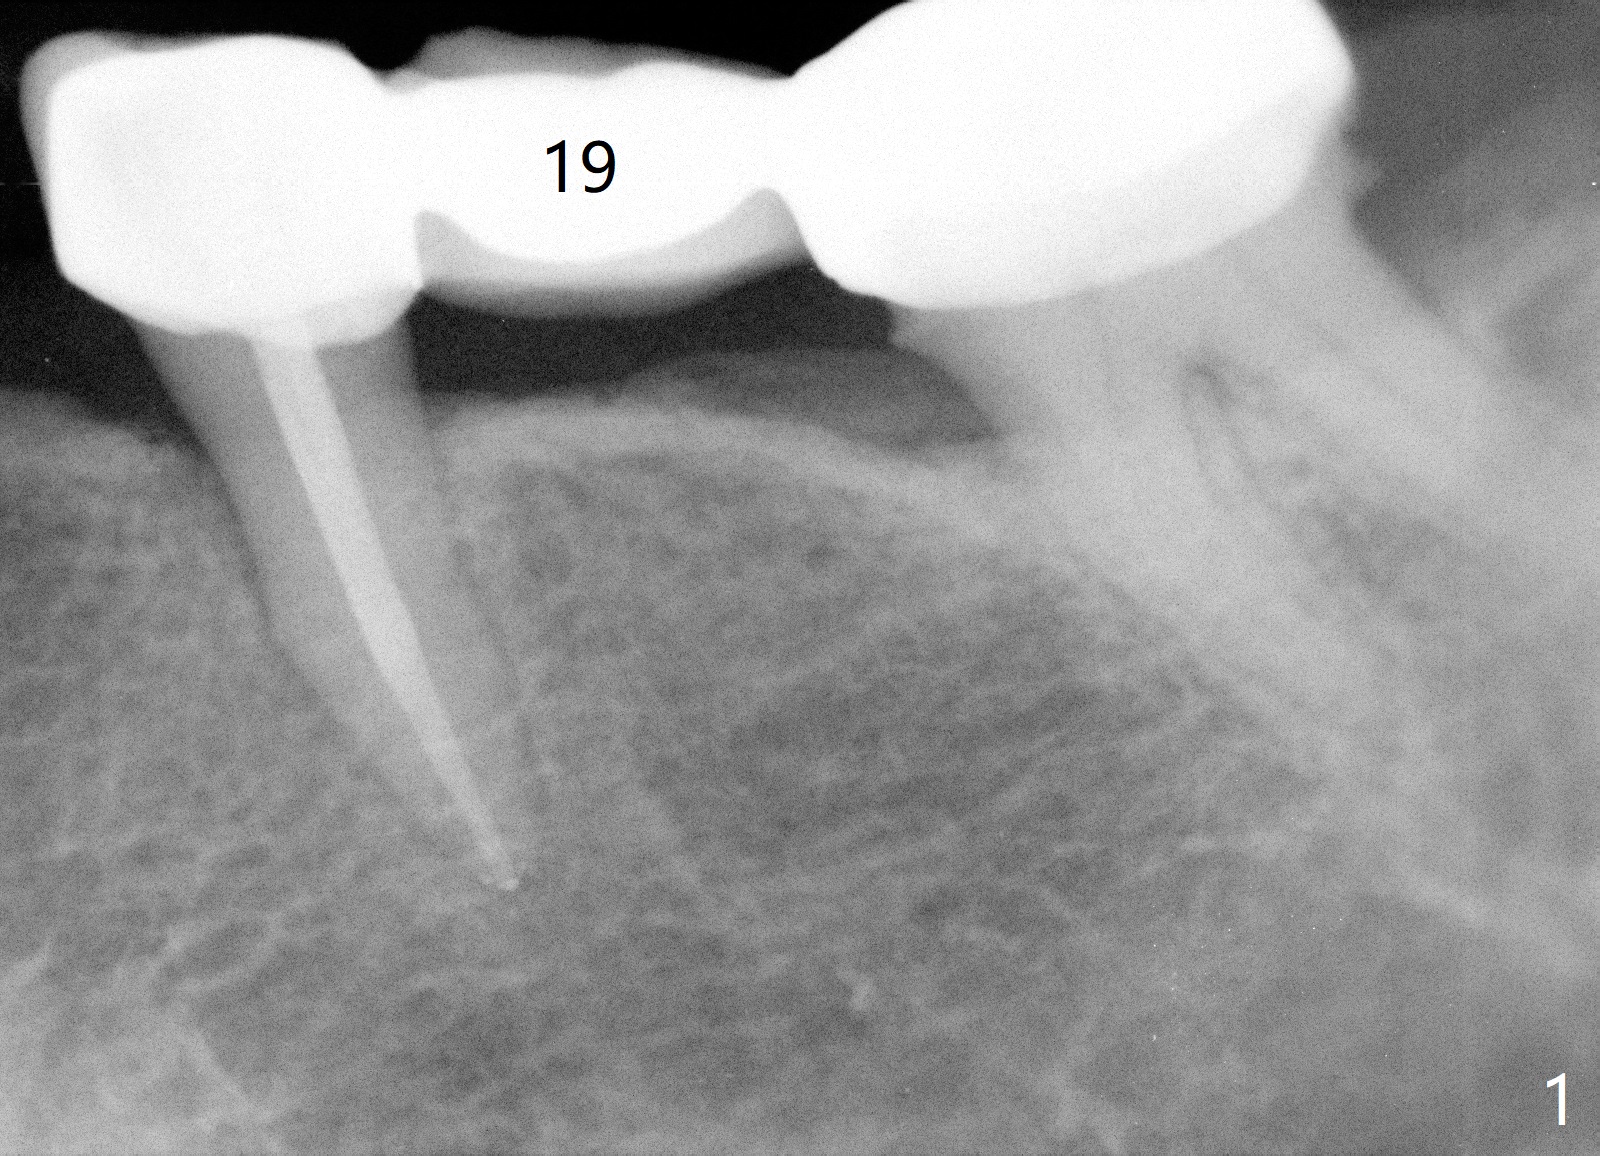

A 65-year-old woman will return for implant placement at #19 pontic area (Fig.1) nearly 3 months post implant placement at #20 (Fig.2). Since the edentulism should be long standing, the ridge must be narrow buccolingually. On the other hand, the ridge is long coronoapically (Fig.2). Ridge reduction will be conducted. If the width can be gained for 5 mm with less than 3 mm height reduction, a 4x7(3) mm Magicore will be placed. Otherwise a long 1-piece implant is to be chosen. The narrow implant (3 or 4 mm) is justifiable because of relatively small mesiodistal space at the pontic. Prepare implant positioners of 3 and 4 mm.